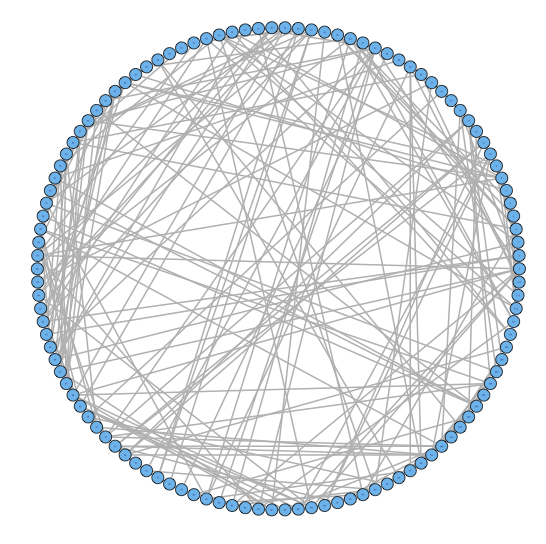

2.2 Challenge I: Two Levels of Network Variability

For our two-level problem (1.1.1), we must account for two sources of network variability when conducting population inference: (i) variability between subjects within a group and (ii) variability of the network selection procedure within a single subject. To see this, let us study a real multi-subject fMRI example. In Figure 2, we show estimated functional brain networks for subjects from the UCLA fMRI ABIDE data set INDI (2013). We describe the details of this data set, our pre-processing, and brain parcellation later in the Case Study in Section 5. In the top and middle panels, we estimate brain networks for each subject using graph selection methods for Gaussian graphical models (see Section 3.1 for details) and plot these as circle graphs to easily visualize network differences. It is clear that there are not only differences between autistic subjects and control subjects, but there is also large heterogeneity across subjects within each group. This is well-known in the neuroimaging literature (Milham et al., 2012; Nielsen et al., 2013), and makes finding statistically significant differences between subject groups much more challenging.

Less well studied in neuroimaging, is the second source of variability which arises from estimating networks for each subject instead of directly observing the networks. In the bottom panel of Figure 2, we re-estimate brain networks for a single control subject with bootstrap resampled data. It is clear that there is major intra-subject variability arising from our graph selection procedure. Indeed in neuroimaging, test–re-test studies which conduct brain imaging on the same subject in repeated sessions have shown high variability in the subject’s estimated brain networks (Wang et al., 2011). This also motivates the necessity of using a two-level model like (1.1.1) for population network inference as opposed to the one-level model and test statistics of the standard procedure.